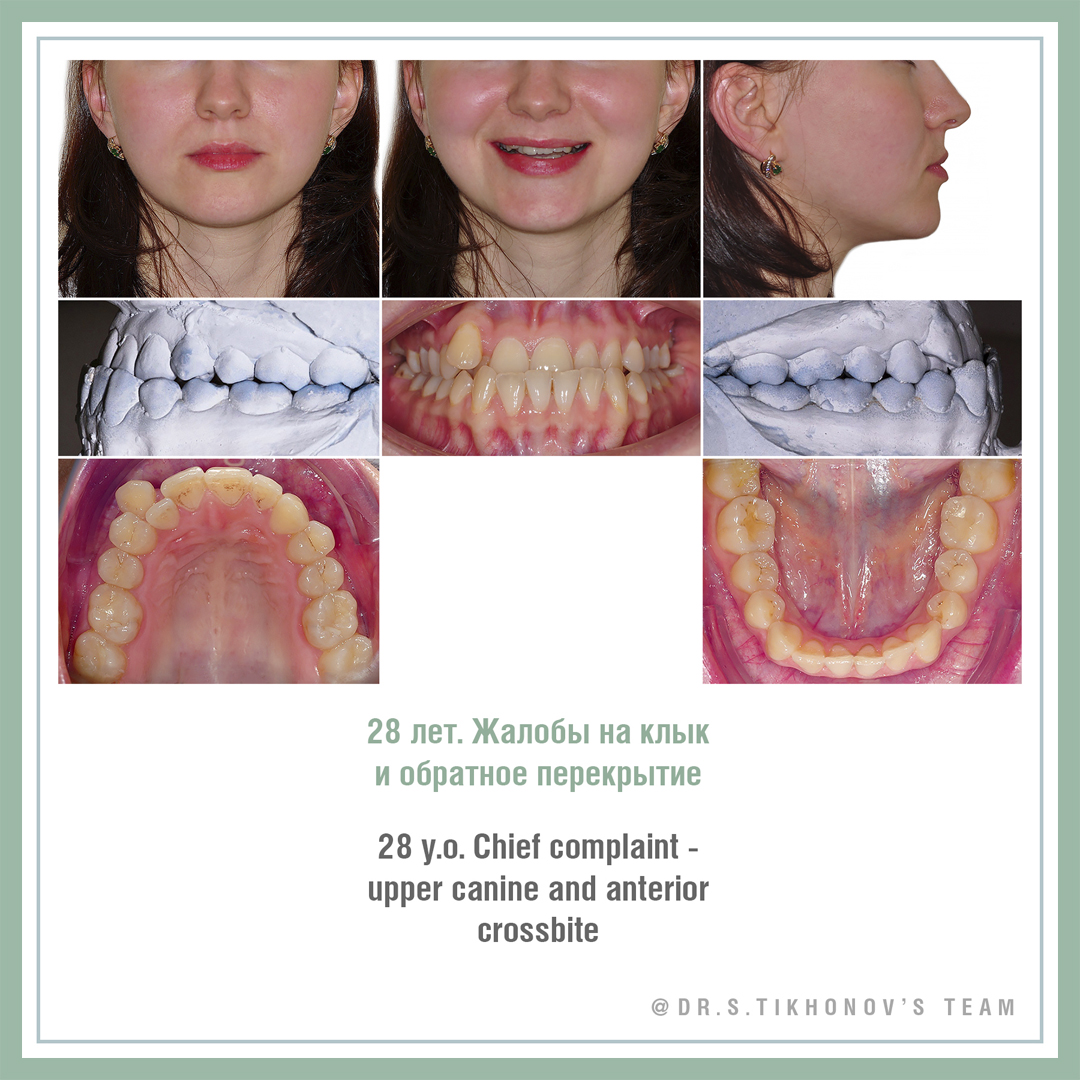

Конечно, я пару раз показывал ее на семинарах, но не все были, не все помнят. Взрослая, с мезиальным прикусом, беспокоит клык и обратное перекрытие, на лицевые признаки жалоб нет. Подробнее диагностическая информация на слайдах.

Сложность тут не только в мезиальном прикусе и перекрытии, но и в очень сильном дефиците места для 13. В Школе мы обсуждаем 5 способов создания места. Интересно, какие подходят здесь?

28 y.o., skeletal class 3, chief complaints: 13, anterior cross bite, facial appearance is ok! Please, share your Tx options in comments! Don’t be shy! This is the training account!